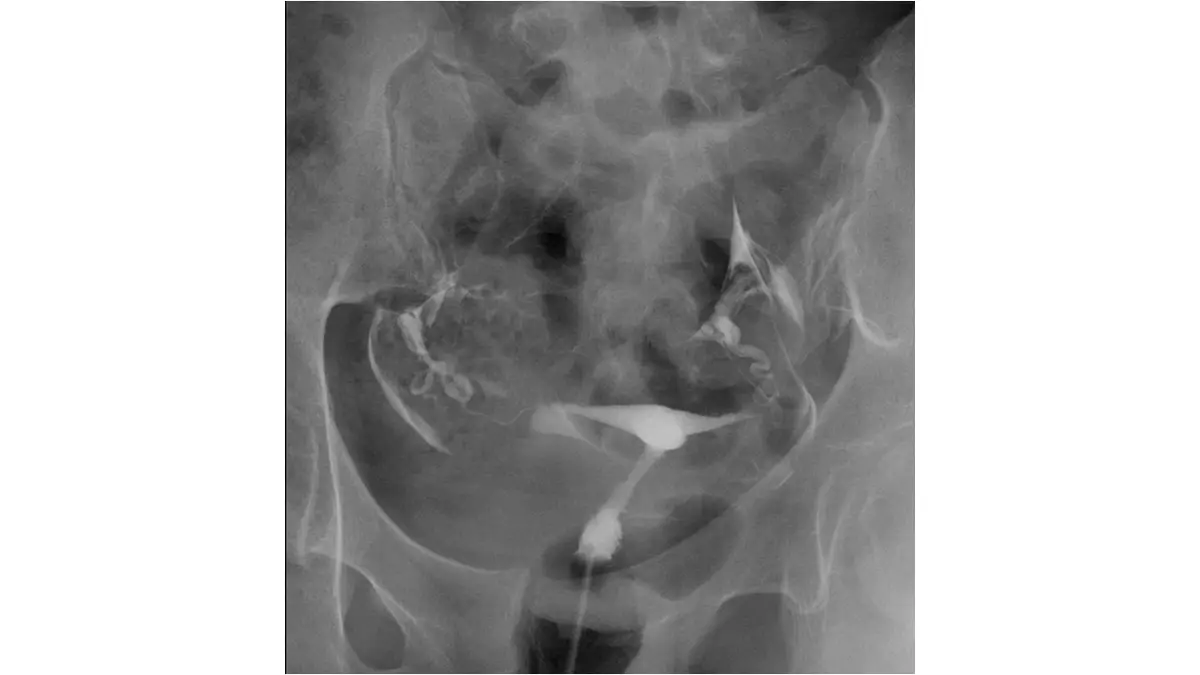

不孕症女性,子宮輸卵管攝影檢查呈現如圖,下列敘述何者最正確?

本圖為子宮輸卵管攝影(HSG)骨盆腔前後位 X 光片,顯示以下所見:

子宮腔:子宮腔(正中央白色不透明顯影劑充填區)輪廓可辨,呈近似倒三角形的充填型態,腔壁尚稱平整,未見明顯局限性充填缺損(filling defect),不支持子宮內粘連或內膜息肉的存在。子宮頸管可見造影劑充填,子宮頸部分無明顯狹窄表現。

輸卵管:雙側均可見顯影劑自子宮角(cornual region)流入輸卵管,沿兩側延伸至骨盆腔。輸卵管走行可見,最重要的是:兩側輸卵管末端可見顯影劑溢入腹腔(peritoneal spillage),表現為造影劑在兩側卵巢/輸卵管傘端周圍散布於腹腔,形成「雲霧狀」彌散影。這是確認輸卵管暢通最關鍵的 HSG 所見。

結論:影像符合兩側輸卵管暢通(bilateral tubal patency)的典型 HSG 表現——雙側均有腹腔內顯影劑溢出,且子宮腔形態正常,無明顯解剖異常。